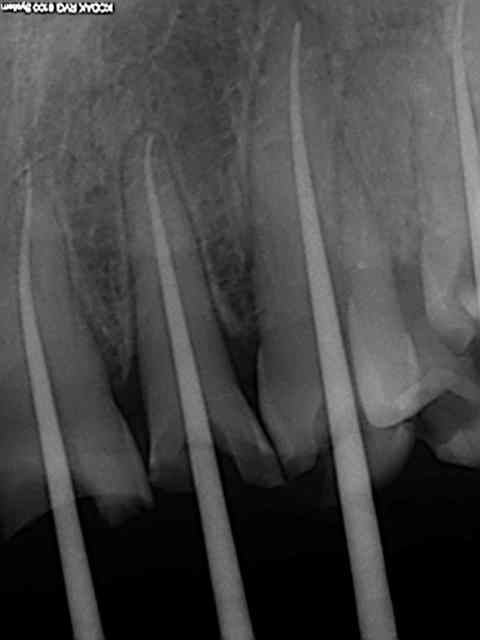

Zoom incisives eb4rim - Eugenol

Retraitement et cour prov ej8sen - Eugenol

Canaux calcifi s e685ou - Eugenol

Avec provisoires o4ho8c - Eugenol

Sur les monoradiculées, les tenons sont un peu trop courts. Avec les années, si l'os alvéolaire diminue, les risques de fractures de racines augmentent lorsque le bout du tenon se retrouve au niveau du rebord alvéolaire.

je fait extrêmement peu de tenon, mais tu nous présentes un travail soigné au moins d'un point de vue radiologique, sur la technique endo intrinsèque je laisse le soin a chacun de se faire une opinion